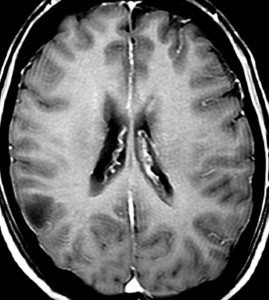

びまん性星細胞腫のIDH 野生型 wild type ゆっくり増大するものがあるか?

無症状で発見されたびまん性星細胞腫です。右側はその6年後,非常に緩徐に増大しています。良性のびまん性星細胞腫グレード2を疑い,手術で周囲脳も含めて完全摘出 supratotal resection しました。病理診断は,びまん性星細胞腫 WHO グレード2,MIB-1は2%,1p/19q欠失なしでした。大学病院の病理部ですが当時はIDHの検査をしていません。

術後4年目のものです。深部に小さな再発像が出現しました。これも予想の範囲内でした。これも手術で全摘出しました。普通ならあとは経過観察をするのみです。

しかし,病理診断では IDH1, IDH2ともに変異なし,野生型 wild typeでした。1p/19q non-codel, ATRX mutantです。急速な悪性化が懸念されましたので術後に局所放射線治療を加えました。それ以降は腫瘍再燃はありません。

経過は,IDH mutant diffuse astrocytoma WHO grade 2です。でも,再発像でwild typeでした。malignant transformationなのか?このような例をどう解釈してよいのか不明です。